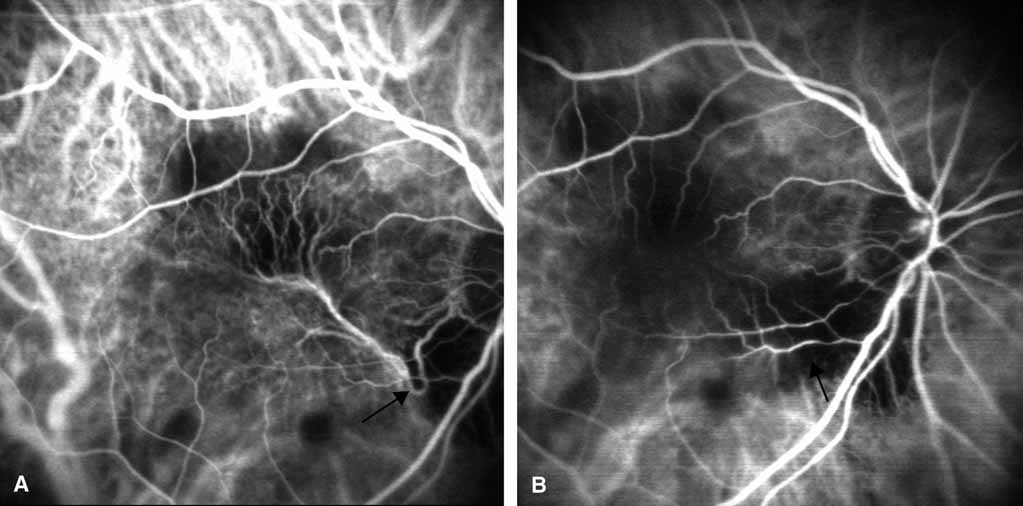

Fig. 11 A. Pretreatment scanning laser ophthalmoscope high-speed indocyanine green angiography showing a well-delineated choroidal “feeder” (arrow) vessel supplying a large subfoveal neovascular complex. B. Posttreatment SLO-ICGA with laser photocoagulation applied to the feeder only (arrow) shows a lack of blood flow through the entire neovascular complex.

Choroidal Feeder Vessel Treatment

Using SLO-based ICGA, investigators have been able to identify choroidal “feeder” vessels of AMD-related subfoveal choroidal neovascularization. The SLO allows for rapid image acquisition with rates of up to 20 frames per second. This allows for differentiating choroidal arteries from veins, which is not possible with fundus camera-based ICGA. Using SLO–ICGA and concentrating on the early choroidal filling phase, investigators have been able to identify choroidal vessels that directly feed CNV in selected cases (Fig. 11) Treatment of these “feeder” vessels with laser photocoagulation may or may not result in long-term involution of CNV.75–79 Further study with this treatment approach is needed.